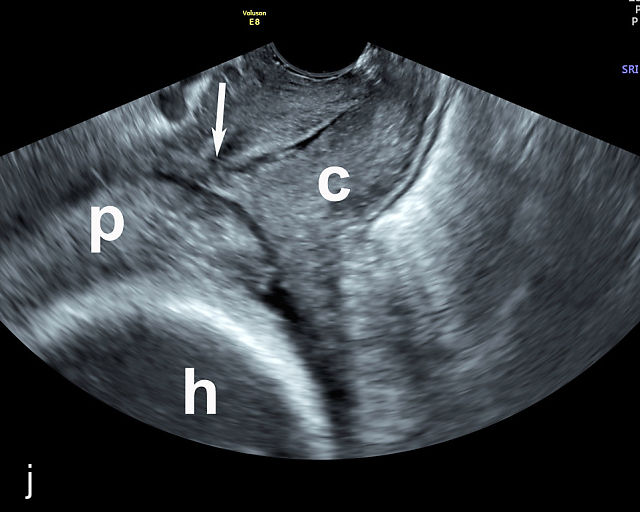

5

Placenta previa and low-lying placenta. (a) Transabdominal grayscale ultrasound image suspicious for placenta previa. The placenta (PL) appears to overlie the internal cervical os (CX). Note the time stamp: 2:19:37. (b) Transvaginal ultrasound of the same patient taken approximately 50 minutes later. Note the time stamp: 3:10:25. The internal os and the lower placental edge are both clearly seen, and the placenta does not overlie the internal os. Because the lower placental edge is 1.93 cm from the internal os, it will likely resolve by the third trimester. (c) Transabdominal grayscale ultrasound of placenta previa. The placenta (p) covers the cervix, but the cervix, especially the internal os, cannot be visualized due to shadowing. (d) Transabdominal grayscale ultrasound of placenta previa. The placenta (p) covers the cervix (c) but shadowing obscures adequate visualization. The internal os is indicated by the arrow. (e) False-positive image of placenta previa on transabdominal grayscale ultrasound. The bladder (b) is full, pushing the anterior and posterior walls of the lower uterine segment (ls) together making it appear that the placenta (p) overlies the internal os of the cervix. In reality, the line depicted by the arrowheads is where the anterior and posterior walls of the lower segment are in proximity to each other. The cervix is much lower and is obscured by shadowing (c). (f) Transabdominal grayscale ultrasound image of placenta previa. The placenta (p) covers the cervix (c), but the cervix, especially the internal os, cannot be visualized due to shadowing. b, bladder. (g) Transvaginal grayscale ultrasound image of placenta previa. The placenta (p) completely covers the internal os (arrow) of the cervix (c). The internal os can be seen clearly. h, fetal head. (h) Transvaginal grayscale ultrasound image of posterior low-lying placenta (p). The lower placental edge is clearly seen and is 1.56 cm from the internal os (arrow) of the cervix (c). The placental edge and the internal os are clearly seen. h, fetal head. (i) Transvaginal grayscale ultrasound image of a posterior placenta previa (p). The internal cervical os is clearly seen (arrow). c, cervix. (j) Transvaginal grayscale ultrasound image of an anterior placenta previa (p). The internal cervical os is clearly seen (arrow). c, cervix; h, fetal head. (k) Transvaginal grayscale ultrasound image of a posterior placenta that was thought to be low-lying on transabdominal sonography but could not be adequately assessed. This examination clearly shows the lower edge of the placenta (p) to be 2.18 cm from the internal os (arrow) of the cervix, firmly establishing that the placenta is not low-lying and allowing the patient to undergo labor safely and deliver vaginally. c, cervix. (l) Transvaginal grayscale ultrasound image of placenta previa. The placenta (p) completely covers the internal os (arrow) of the cervix (c). The internal os can be seen clearly.